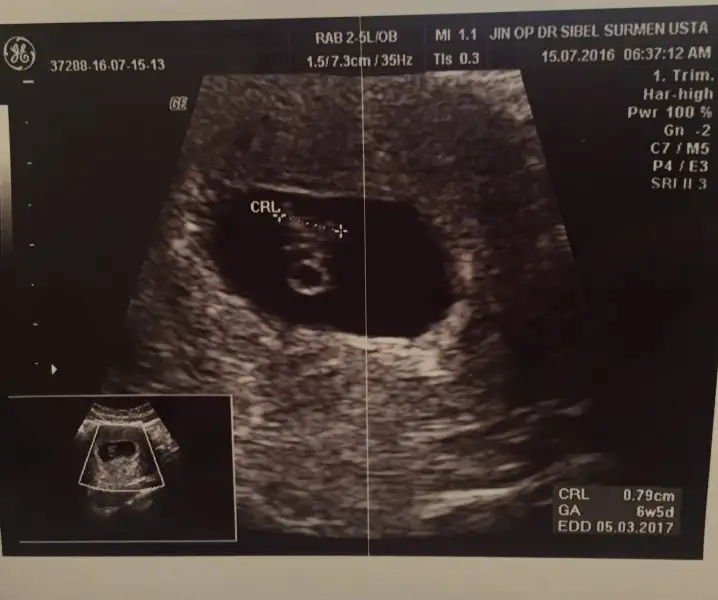

Merhaba canımm acaba benim bebeğimin cinsiyeti nedir :) 6+2ydik bu ultrasonda karındanHavalianne__

Keseye gore erkek canim..